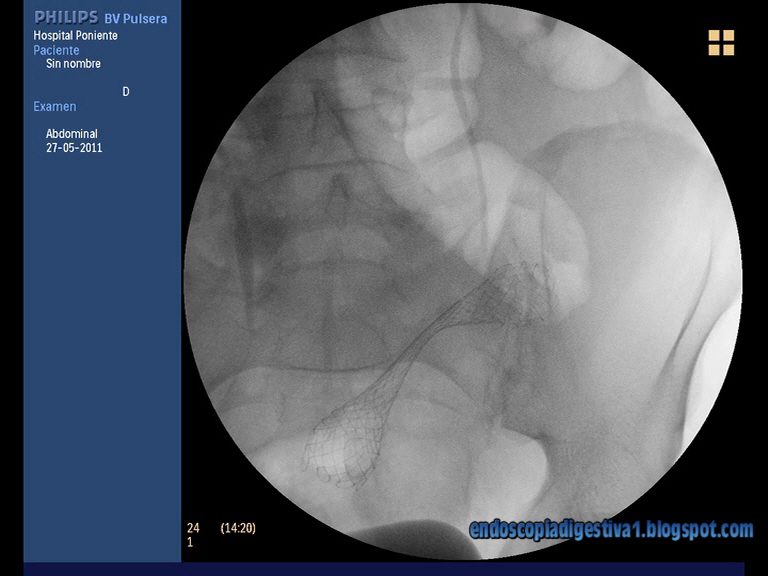

Como ya se ha publicado en este blog, una de las indicaciones mas frecuentes del uso de prótesis no recubiertas metálicas en el colon es la oclusón aguda de éste por una neoplasia. En muchos casos se colocan como «puente a la cirugía resectiva con reconstrucción en un solo tiempo de tránsito colónico», evitando de esta manera (en muchos casos) la realización de dos intervenciones quirúrgicas (la primera donde suele dejarse una colostomía de descarga y la 2ª para la reconstrucción final del tránsito intestinal). Aunque la técnica no es muy compleja de realizar, no está exenta de complicaciones, algunas de ellas graves como la perforación. Dentro de las localizaciones donde se pueden colocar una prótesis de estas características, sin duda, las mas agradecidas son aquellas situadas entre la unión rectosigmoidea y el colon descendente (aunque también se han conseguido buenos resultados en el ángulo esplénico e incluso hepático). Es importante intentar elegir la longitud adecuada de la prótesis de acuerdo a la de la estenosis (los diámetros existentes en el modelo Wallflex de Boston Scientific son las de 6, 8 y 12 cm) e intentar colocarla lo mas centrada posible para que la fuerza radial se ejerza de forma específica en la zona de interés. Nosotros usamos la técnica combinada fluroscópica-endoscópica, donde tras pasar la estenosis con una guía rígida y gruesa (p.e jagwire 0.035″ de 450 cm de longitud con ayuda de un canulotomo o esfinterotomo), medimos su longitud anclando un balón de fogarty de 18-20 mm en el margen proximal de la estenosis (tras inyectar abundante contraste) y con la punta del endoscopio como margen distal de ésta. Según la longitud calculada (basada en una regla de tres sobre el calibre del colonoscopio (1.2 cm), damos unos 2 cm mas por cada lado. En resumen, como en este caso, que la estenosis medía unos 3.5-4 cm, usamos una prótesis de 9 cm.